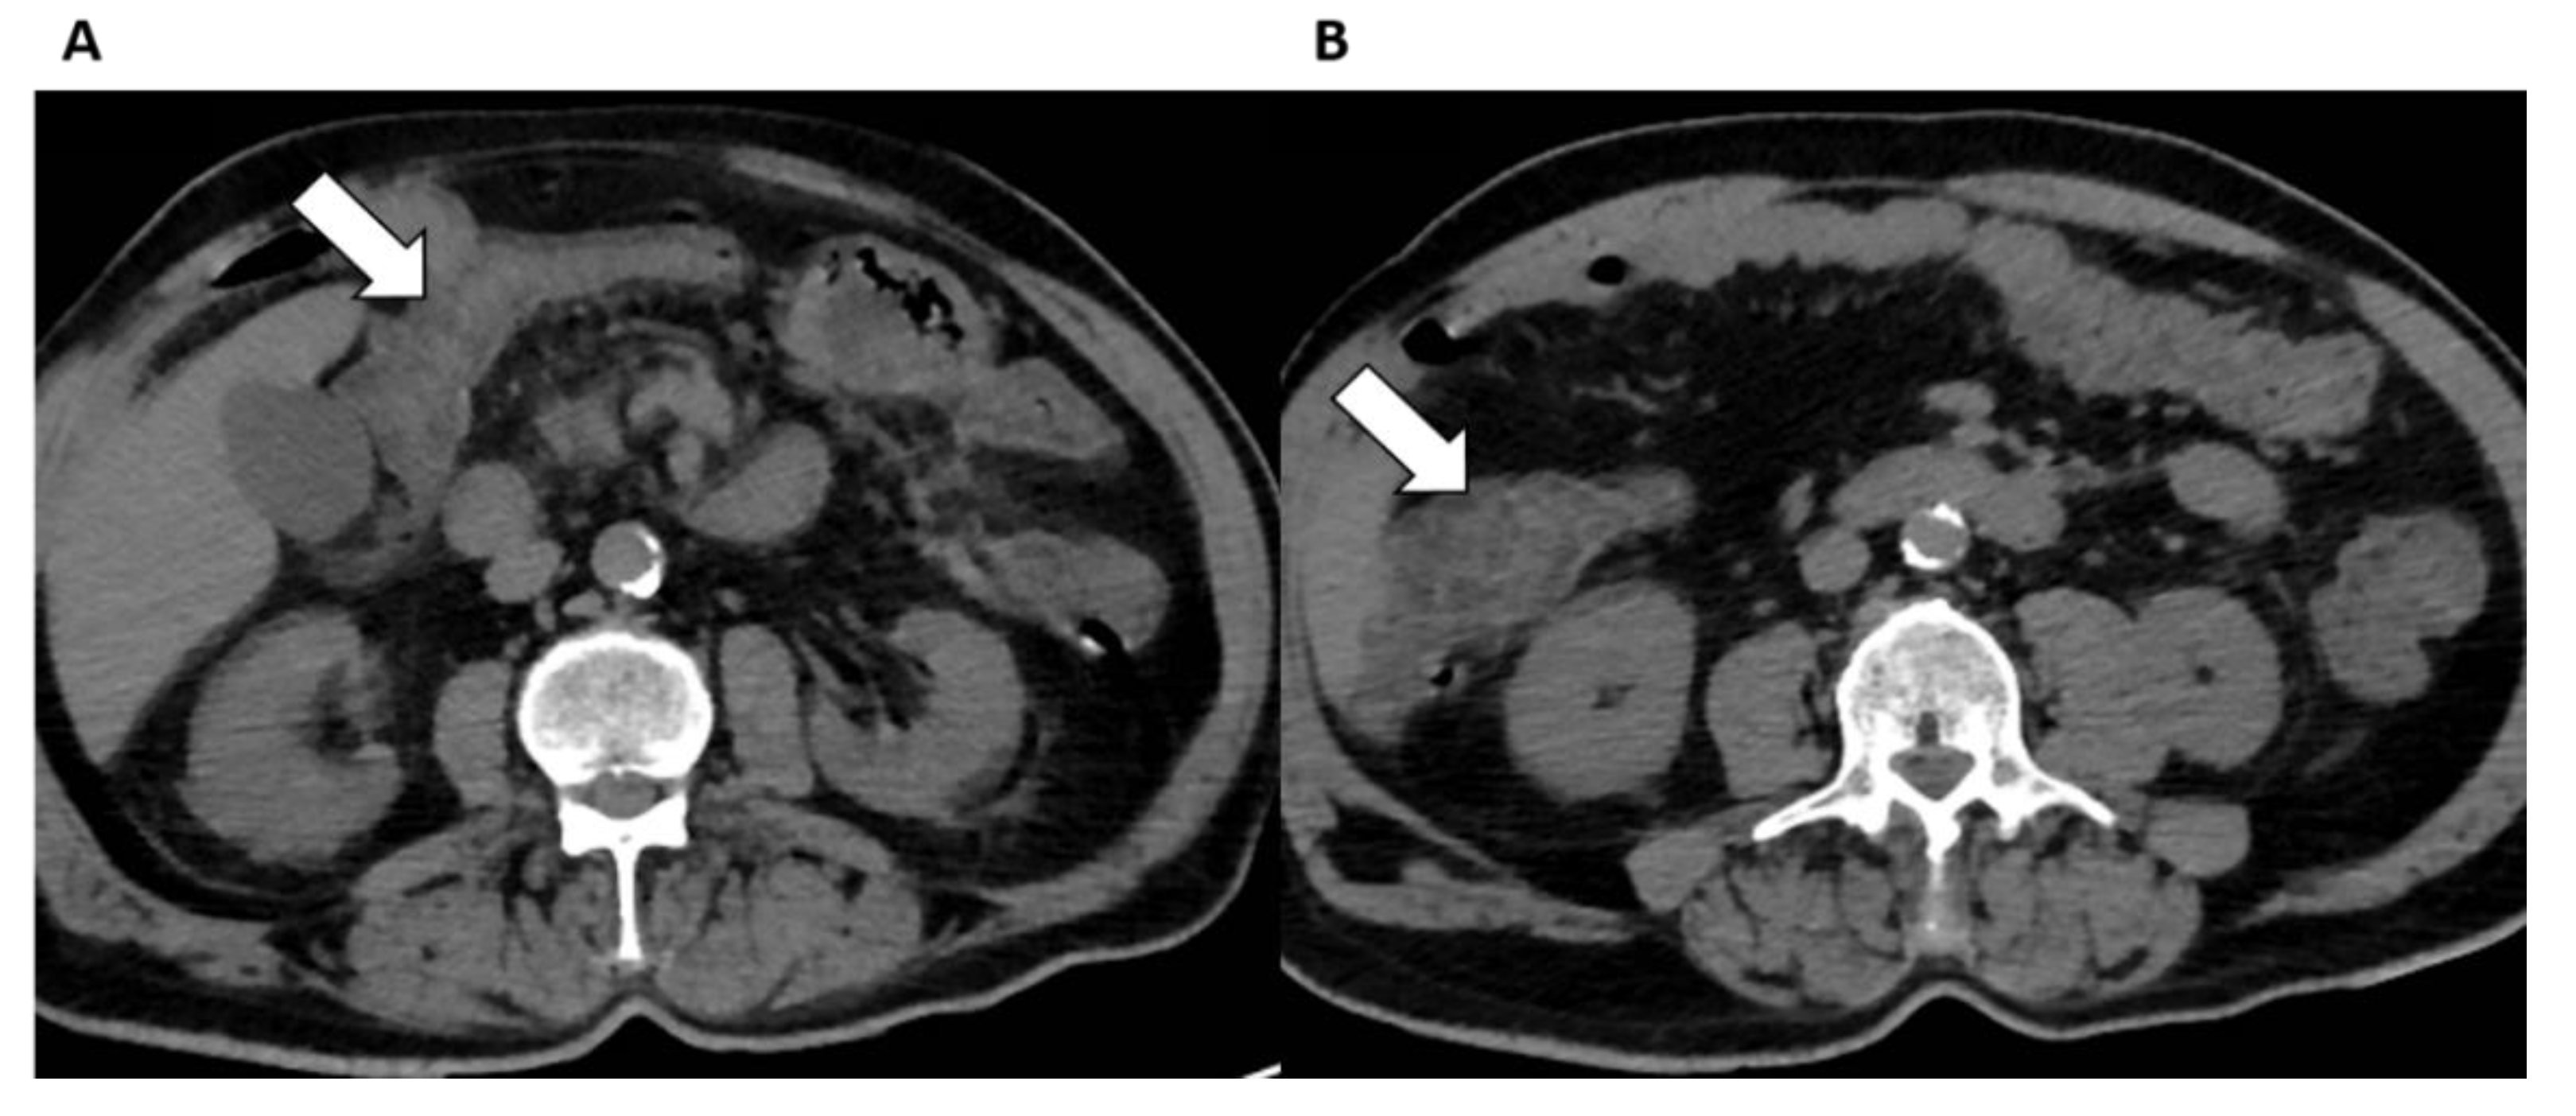

5.4. Gastrointestinal Tract

- Keshavarz, P.; Rafiee, F.; Kavandi, H.; Goudarzi, S.; Heidari, F.; Gholamrezanezhad, A. Ischemic gastrointestinal complications of COVID-19: A systematic review on imaging presentation. Clin. Imaging 2020, 73, 86–95. [Google Scholar] [CrossRef]